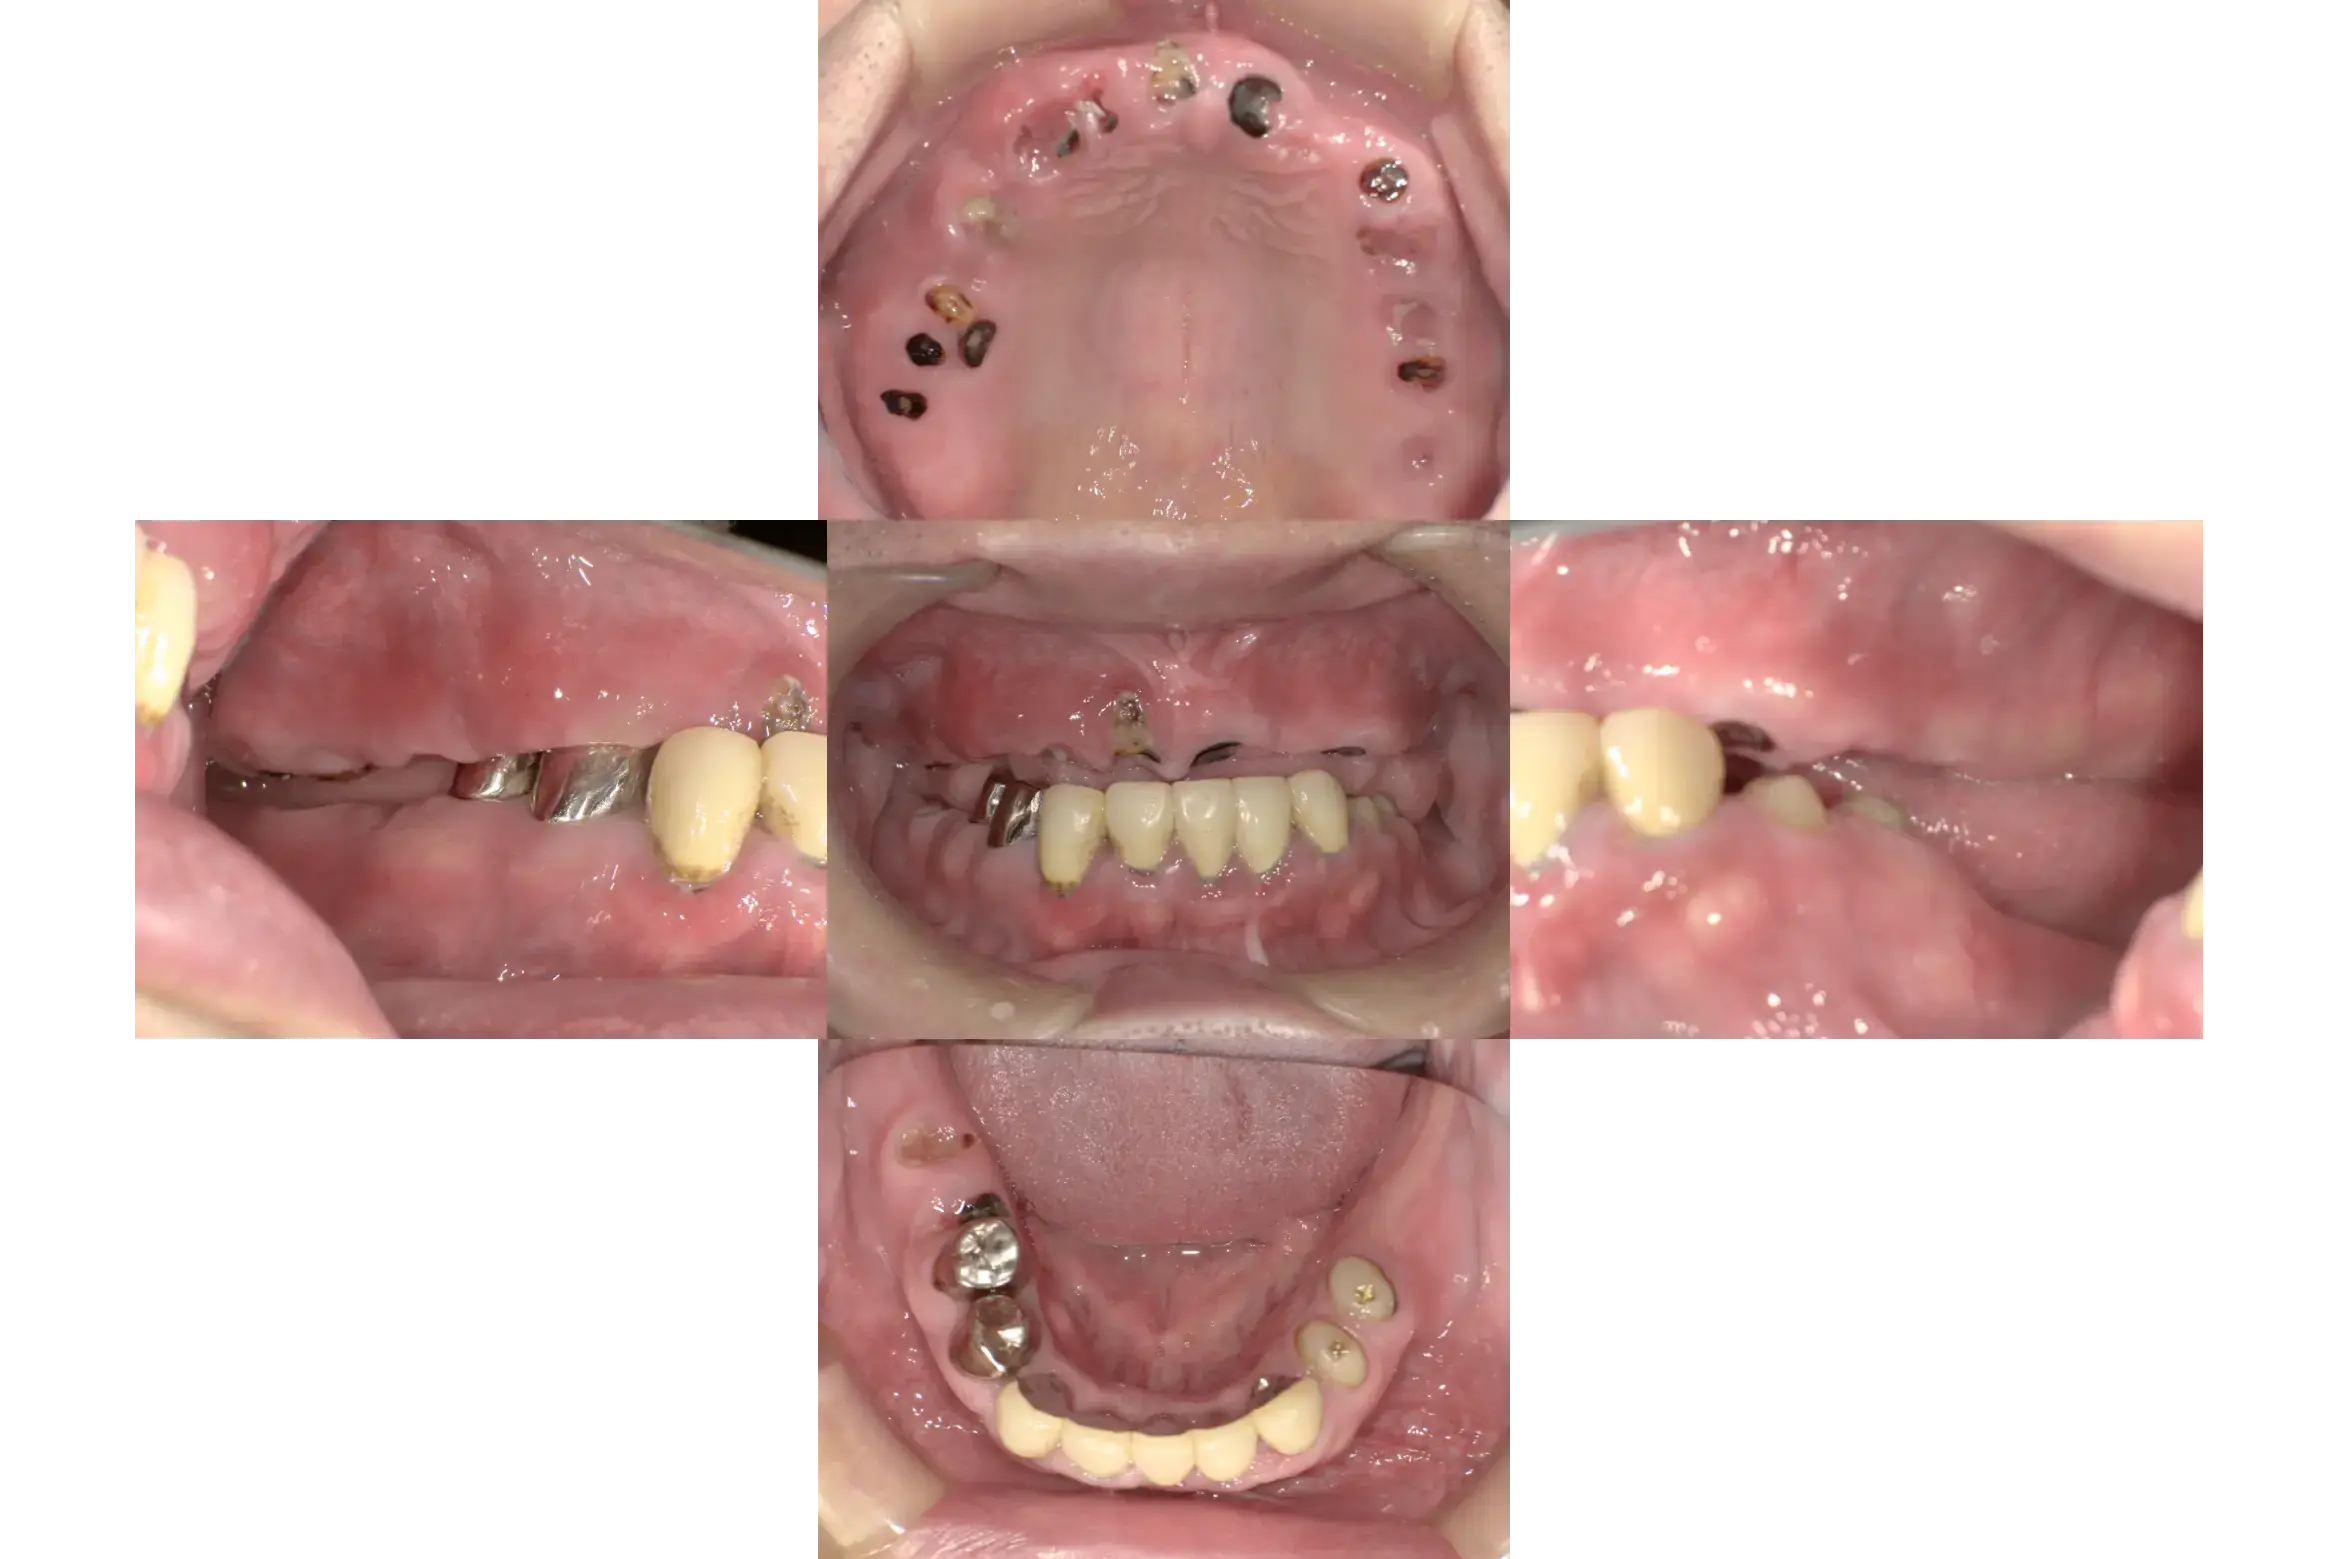

| 治療ケース | 骨造成(GBR)、インプラント埋入、オールセラミッククラウン、all on 4 |

| 症状 | 咬みにくい |

| 治療結果 | 歯のない所を治療したいとの主訴で来院されました。虫歯や破折で抜歯が必要な状態でした。抜歯、骨造成(GBR)を行い待機期間を経て1次手術、2次手術を行いプロビジョナルを装着後問題の無いことを確認して最終上部構造を装着。歯が入った後経過も良く、安定している状態です。 |

| 治療開始月 | 2024年7月 |

| 治療期間 | 約10ヶ月 |

| メンテナンスの頻度 | 3ケ月毎 |